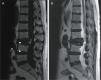

She consulted for low inflammatory back pain lasting 4 weeks, with no history of trauma, fever or constitutional symptoms. The lateral lumbar spine X-ray showed a fracture of L3 due to collapse with intravertebral vacuum phenomenon (IVVF), suggesting vertebral osteonecrosis (ON). Computed tomography (CT) and magnetic resonance imaging (MRI) confirmed this diagnosis (Figs. 1–3). Surgical fixation was performed of the area. The study showed histological signs of bone avascular necrosis: trabecular bone tissue with extensive areas of necrosis, medullary space with proliferation of granulation tissue, few hematopoietic elements, necrosis and cellular debris.

IVVF, although not pathognomonic, is the most characteristic radiographic sign of this entity and often suggests the diagnsis.3,4 This sign reflects the presence of gas within the bone (mainly nitrogen) and in adjacent tissues. IVVF can be seen in radiographs, a linear or crescent-shaped radiolucent image usually located adjacent to the superior endplate, which appears or is enhanced by the extension, and decrease or even disappears with flexion of the spine. Sometimes it can be detected by CT or MRI because of its greater sensitivity.